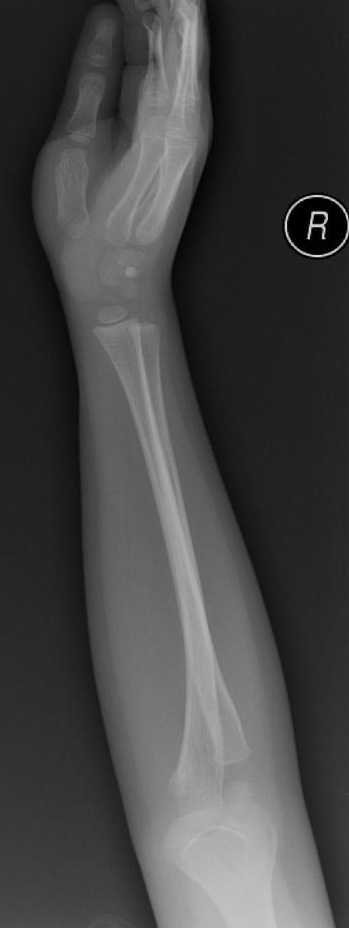

Złamanie typu zielonej gałązki – najczęstszy uraz w wieku rozwojowym

Złamania przedramienia stanowią najczęstszy uraz układu kostnego u dzieci. W codziennej praktyce lekarskiej to właśnie złamanie typu zielonej gałązki (greenstick fracture) pojawia się najczęściej w gabinetach ortopedycznych i na SOR-ach pediatrycznych.

To złamanie niecałkowite, w którym dochodzi do przerwania jednej z korowych warstw kości, przy zachowanej ciągłości po stronie przeciwnej. Elastyczność młodej tkanki kostnej sprawia, że kość nie pęka w pełni – przypomina ugięty, częściowo złamany patyk.

Diagnostyka obrazowa greenstick fracture

Podstawą rozpoznania jest zdjęcie RTG w dwóch projekcjach.

U młodszych dzieci należy wykluczyć urazy wielopoziomowe, a u niemowląt – zawsze rozważyć uraz nieprzypadkowy. W przypadkach wątpliwych pomocne bywa porównawcze RTG drugiego przedramienia.